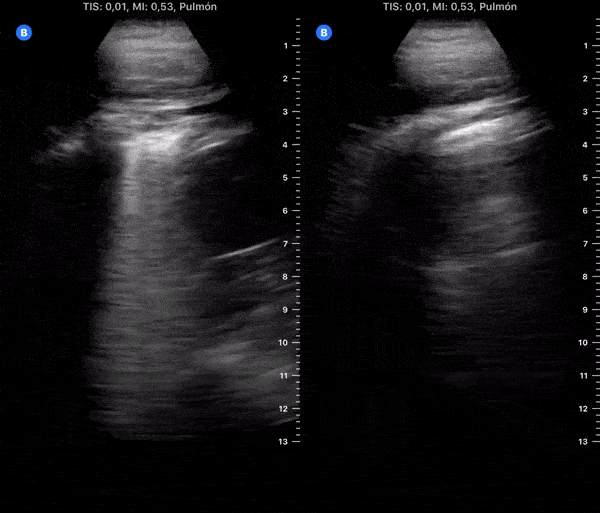

COVID 19 Lung US Disease Progression - Day 16

Day 16 after #COVID diagnosis. Similar dry cough, but with good energy & high spirit. No fever or dyspnea. SpO2 97%. #POCUS update: Improved, less thickened pleura & less bilateral B-lines. @yaletung